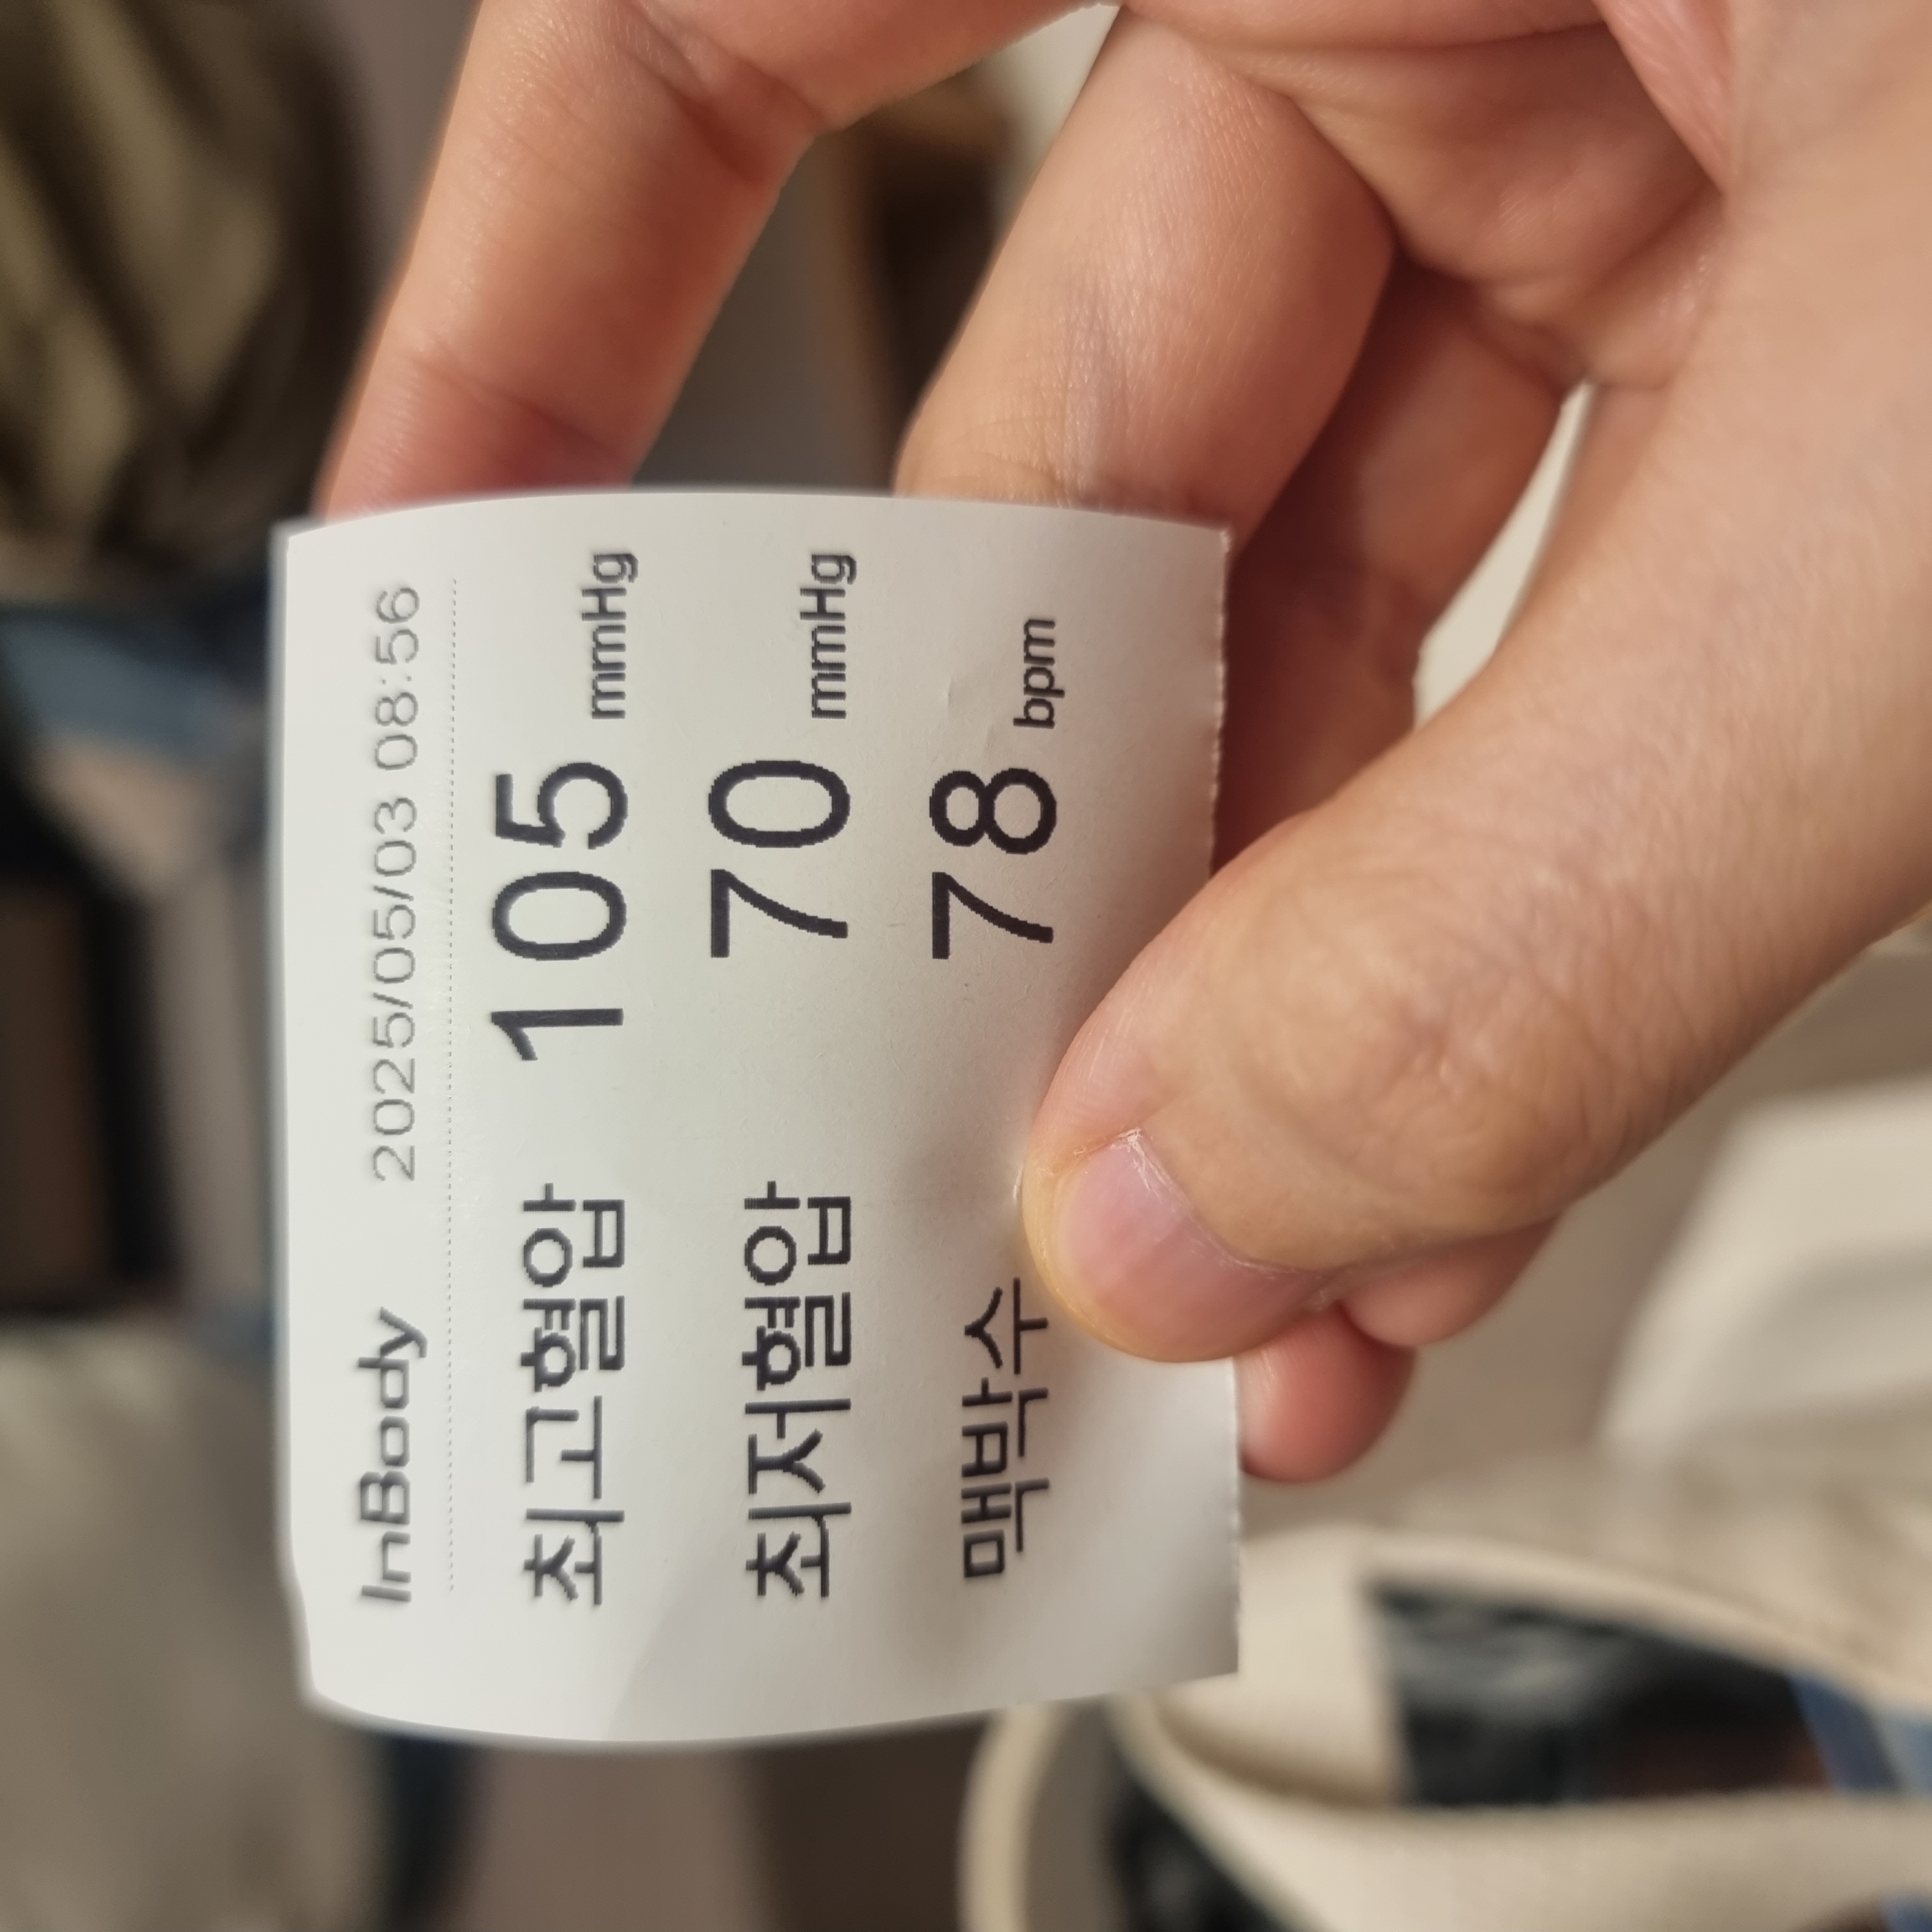

가자마자 혈압+몸무게 쟀구요. 집에 체중계가 없어서 몸무게가 얼마나 늘었을지 진짜 궁금했거든요. 임신전에는 166/48정도로 저체중이어서, 임신한 김에 살이 좀 붙었으면 좋겠다 싶었어요(마른게 컴플렉스)